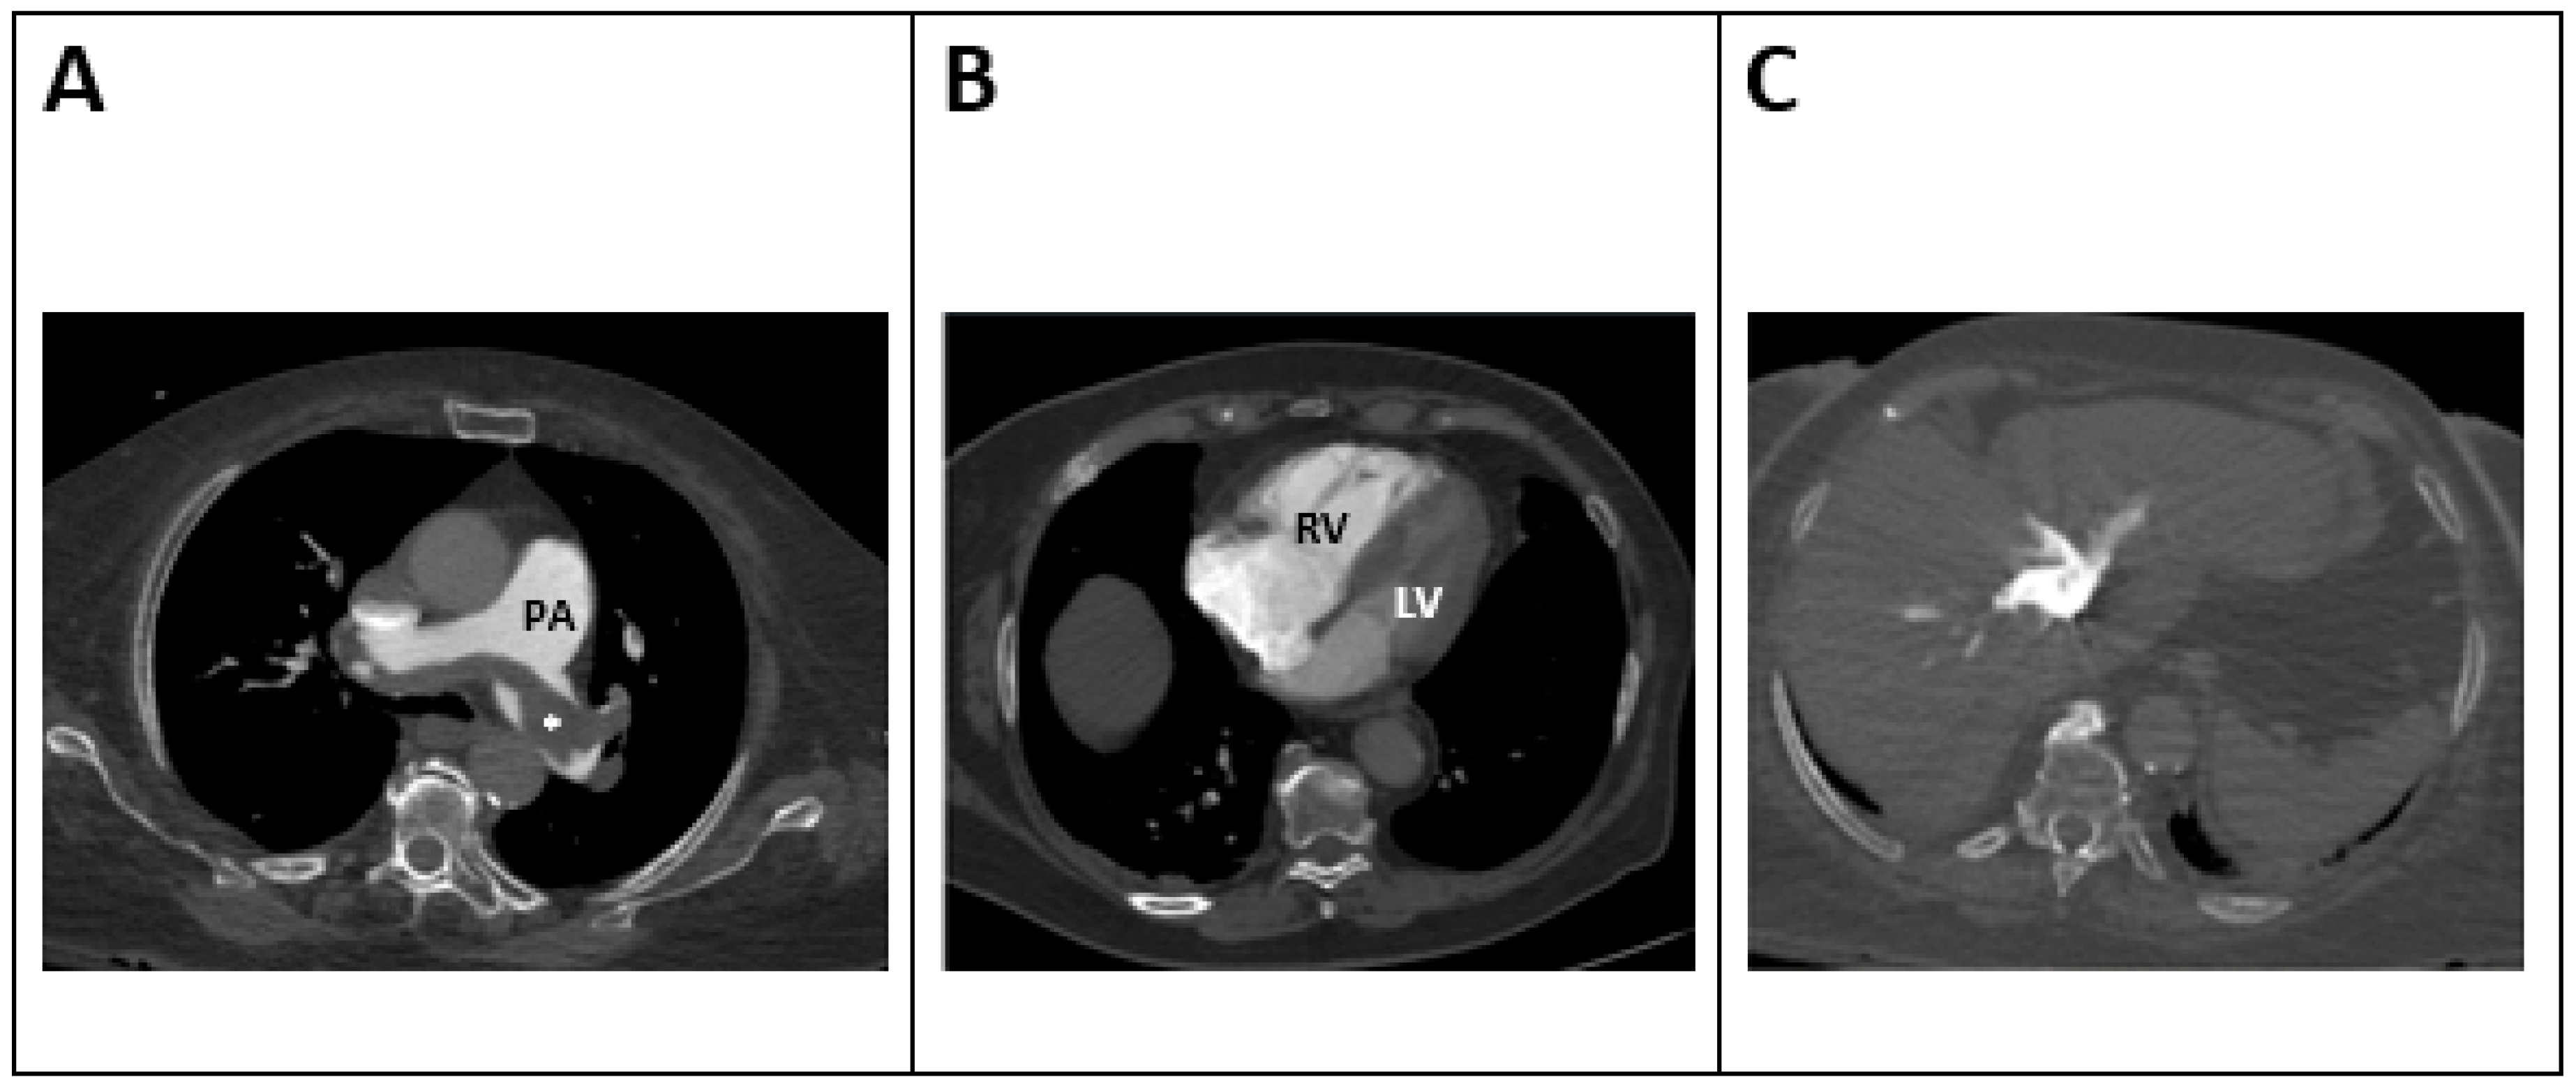

5.3. Computed Tomography (CT) (Figure 2)

| RV/LV RATIO > 0.9 [55] N = 13,162 Figure 2A | RV/LV ratio measured in transverse and 4-chamber view | Association with a 2.5-fold risk of all-cause mortality and a 5-fold risk of PE-related mortality | Validated in assessing RV dysfunction and mortality [56,62], |

| IVC Contrast Reflux [59] N = 365 Figure 2B | Reflux of contrast to IVC and hepatic veins (different degrees of reflux depending on vein involvement) | IVC reflux predicts 30-day mortality [59] | Most trials support its prognostic role in acute PE [59,67]. |

| Decreased left atrial size [65] N = 756 Figure 2C | Left atrium is measured in CT of the pulmonary arteries | Decreased left atrial size (<62 mL) is associated with higher clot load in pulmonary arteries and higher mortality rates [65]. | New technology is emerging evaluating left atrial dimensions and correlation with patient outcome |